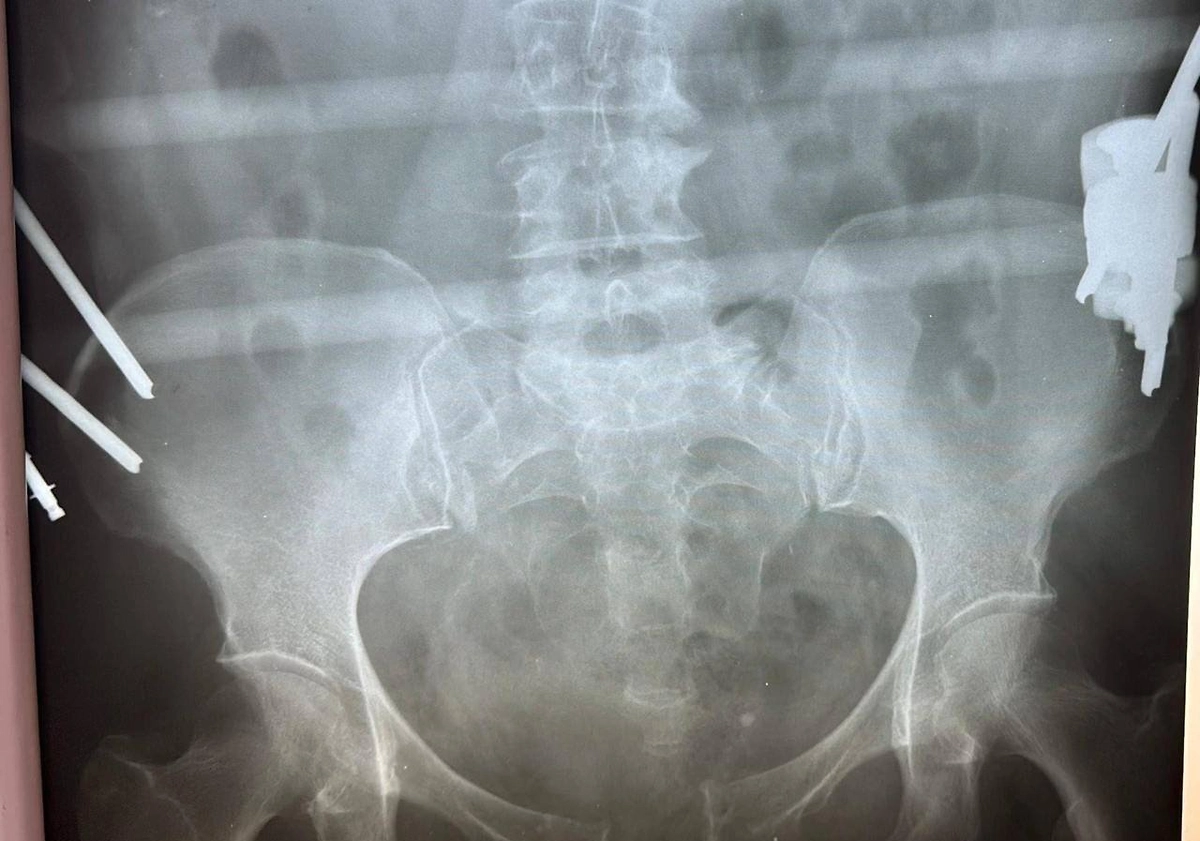

Врачи обнаружили сочетанное повреждение — разрыв лонного и крестцово-подвздошного сочленений, из-за которых тело теряет стабильность и способность выдерживать нагрузку. Медики сразу приняли решение оперировать.

«Мы выполнили остеосинтез — соединили обломки костей специальными пластинами и винтами. Это титан, он безопасен и его не нужно удалять», — объяснил травматолог-ортопед Салман Асламханов.